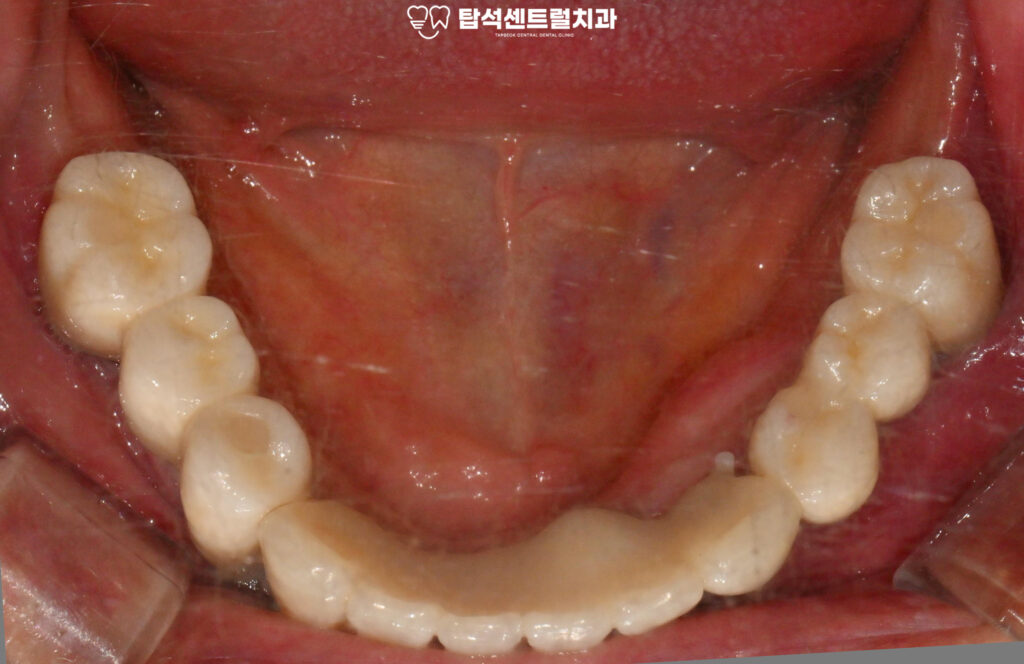

전체 임플란트 치료의 마지막 단계로,

최종 보철을 장착하였습니다.

발치 후 3개월 동안의 골유착 기간을 거쳐

고정력을 확보하였으며

임시보철을 사용하면서 적응된

치아의 고경과 높이에 맞춰

최종 보철이 정밀하게 제작된 모습입니다.